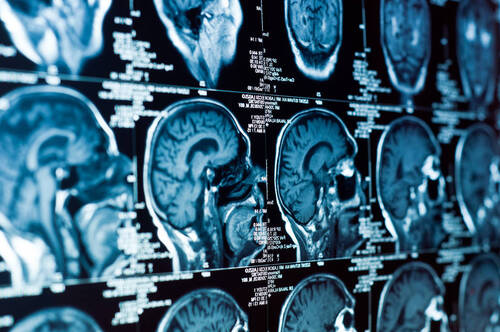

Des investigations dans le cadre du diagnostic ou du suivi sont effectuées avec des moyens tels que l'électroencéphalogramme (EEG), l'électroneuromyogramme (ENMG), l'imagerie cérébrale (Scanner ou IRM), la ponction lombaire, les tests neuropsychologiques. Pour les cas les plus complexes, une partie des investigations donne lieu à une prise en charge interdisciplinaire (collaboration entre plusieurs spécialistes et/ou services). En neurologie, les traitements sont de type médicamenteux, parfois complétés par des mesures de réadaptation en ambulatoire ou en milieu hospitalier (notamment à Porrentruy). Si une opération est nécessaire, un chirurgien (par exemple neurochirurgien) prend le relais.